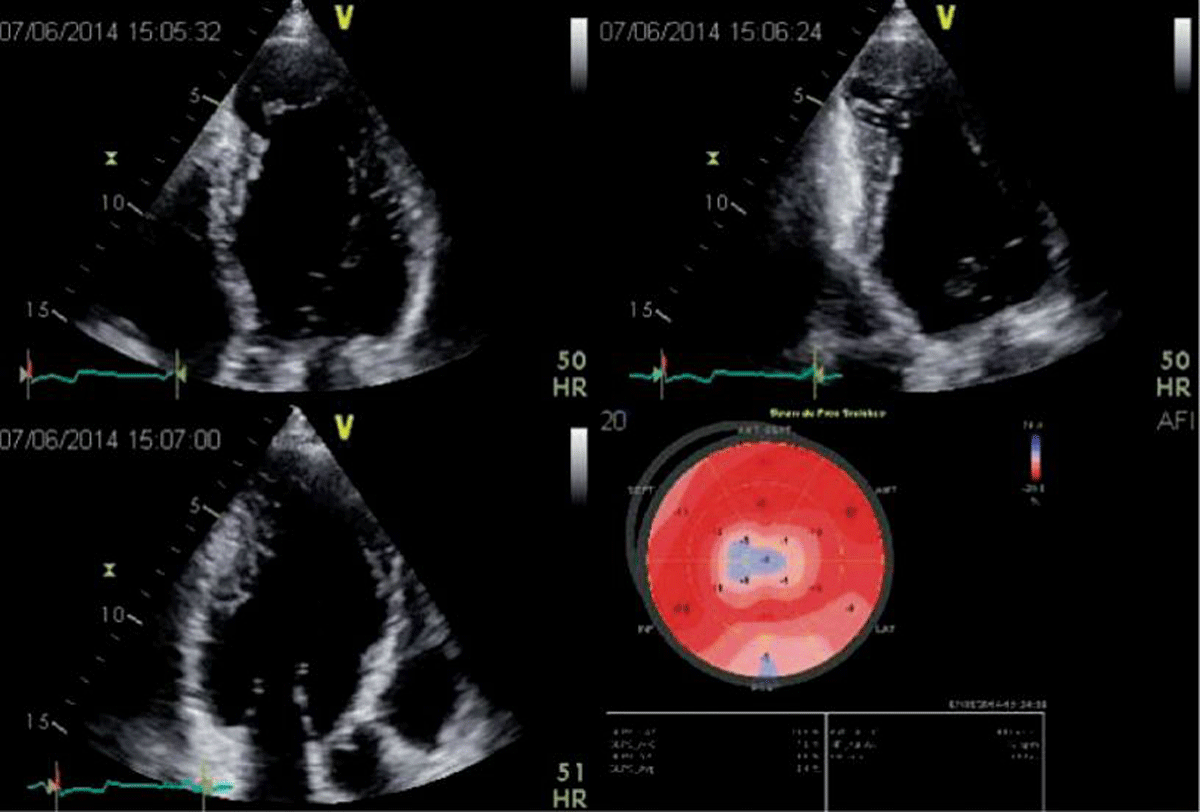

Figure 3

2D apical 4, 2 and 3-chamber views in a patient with Chagas disease and a typical aneurysm. In the 2-chamber view, a basal inferior aneurysm is also present. Longitudinal strain is abnormal in the apex, as well as on the basal inferior wall. Image: Marcia Barbosa. Reproduced with permission of the photographer.